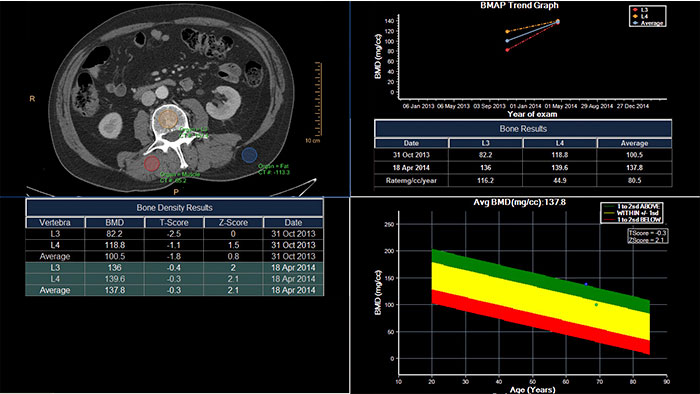

CT Bone Mineral Analysis (BMA)

Track degenerative and metabolic bone disease

CT Bone Mineral Analysis (BMA) is designed to measure bone density in one or multiple time points. Using an internal reference method*, the application reduces reproducibility errors in multiple time point measurements and provides T- and Z- scores which help physicians assess the risk of osteoporosis.

Benefits

- The user can compare a patient’s results to several reference populations.

*Muller DK, et al., Phantom-less QCT BMD system as screening tool for osteoporosis without additional radiation. Eur J Radiol. 2011; 79(3):375–81.